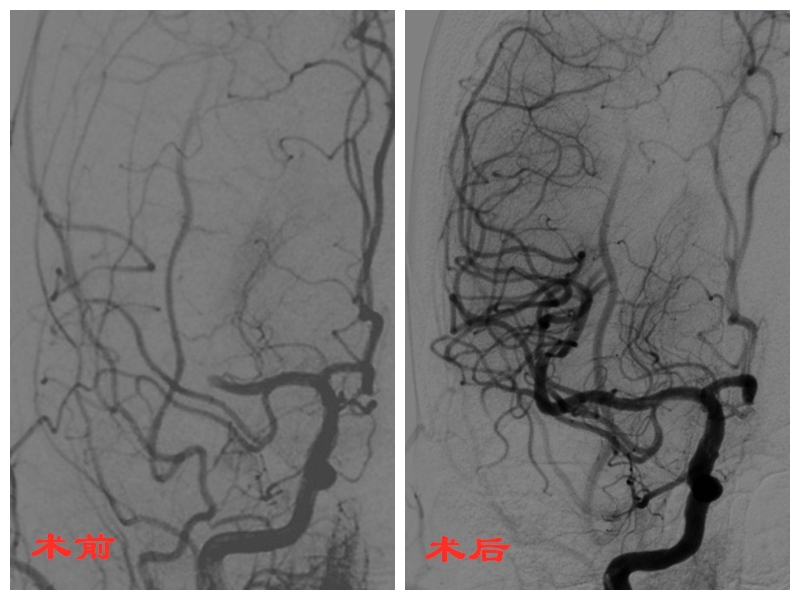

1.急性脑栓塞大血管取栓术:

先后开展大脑中动脉、大脑前动脉、颈内动脉、基底动脉急性闭塞机械取栓术。